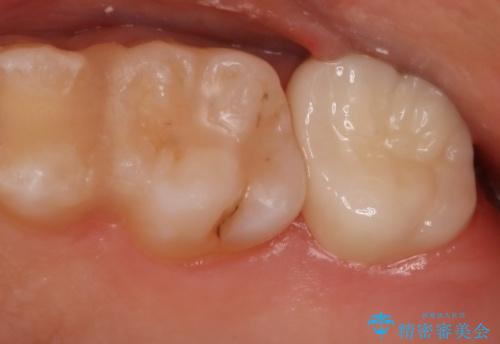

奥歯を治療したい フルジルコニアクラウン

- 99000円(フルジルコニアクラウン+仮歯)費用は治療当時の料金となります

虫歯の範囲が広い場合、大きく削る必要があるので部分的に詰めるインレーではなく、クラウンでの治療になることがあります。